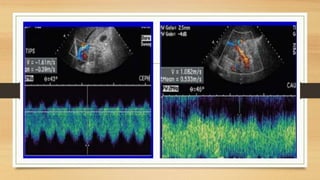

• #58 (c) Spectral Doppler of the flow in the splenic vein shows an antegrade flow with a time average maximal velocity (TAMAX) of 30.7 cm/s and a mean time average velocity (TAMEAN) of 16.6 cm/s. Transverse section through the upper abdomen. (d) Longitudinal section through the middle upper abdomen shows the pancreatic body (P) and the splenic vein (SV). The stomach is marked with “S”